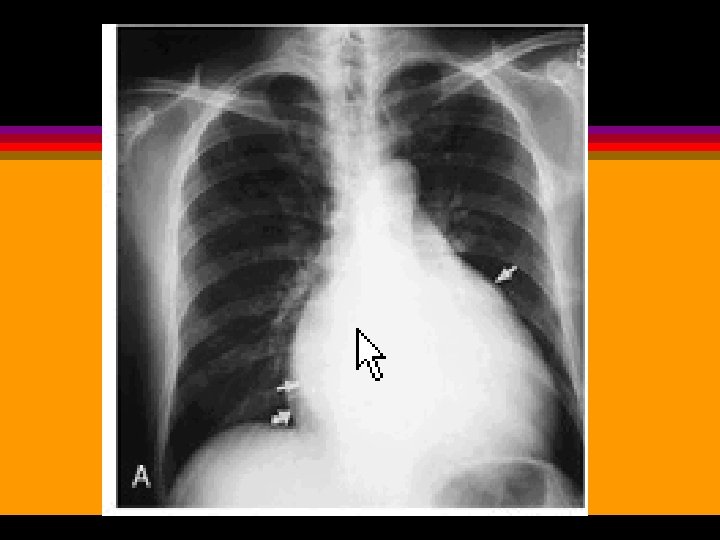

EDEMA PULMONAR AGUDO ESTENOSIS MITRAL (rectificación borde cardiaco izquierdo por crecimiento AI)